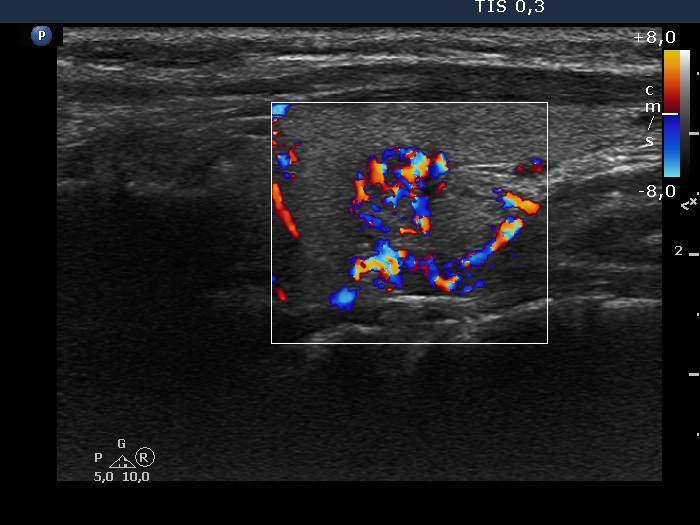

The borders of the nodule - case 2115 (ultrasonographic picture 13)

Left lobe, longitudinal scan, color Doppler mode. This part of the lesion has increased intranodular blood flow, too.